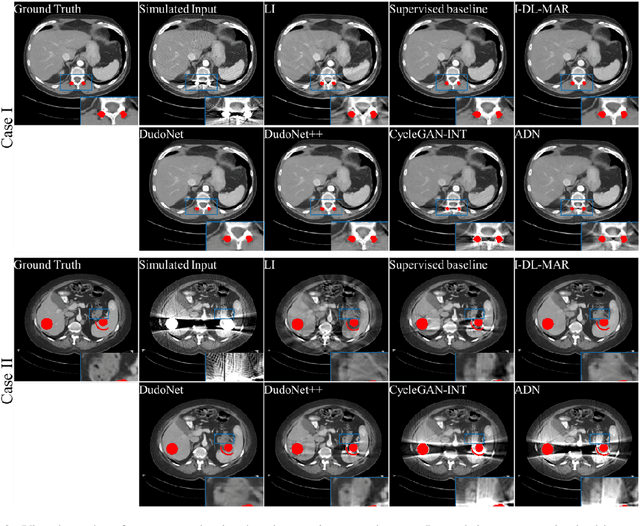

Metal artefacts in CT images may disrupt image quality and interfere with diagnosis. Recently many deep-learning-based CT metal artefact reduction (MAR) methods have been proposed. Current deep MAR methods may be troubled with domain gap problem, where methods trained on simulated data cannot perform well on practical data. In this work, we experimentally investigate two image-domain supervised methods, two dual-domain supervised methods and two image-domain unsupervised methods on a dental dataset and a torso dataset, to explore whether domain gap problem exists or is overcome. We find that I-DL-MAR and DudoNet are effective for practical data of the torso dataset, indicating the domain gap problem is solved. However, none of the investigated methods perform satisfactorily on practical data of the dental dataset. Based on the experimental results, we further analyze the causes of domain gap problem for each method and dataset, which may be beneficial for improving existing methods or designing new ones. The findings suggest that the domain gap problem in deep MAR methods remains to be addressed.